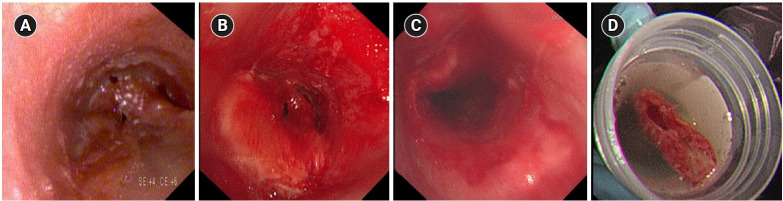

Young woman with recurrent paroxysmal stridor after extubation.